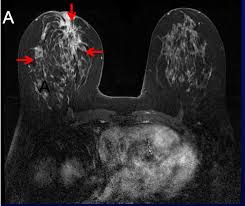

Follow Up Of Patients With Breast Cancer Imaging Of Local Recurrence And Distant Metastases Springerlink from media.springernature.com They can also identify the bone an abdominal or pelvic ct scan can diagnose various types of cancer including breast cancer, colon. See more ideas about ct scan, radiology, medical. Ct scans of the abdomen. The tube is left in place until after your scan, in case you have any problems after having the injection. Interventional radiologists, physicians who specialize in minimally invasive pet/ct scan: Computed tomography (ct or cat) scan. However, the risk from any one scan is small. Ct scan is able to detect large bladder irregularities, but not always small lesions, says dana rice, md, a board certified urologist and creator of the uti tracker mobile app, which helps patients catalog daily urinary tract symptoms, medication.

A ct scan of the upper abdomen showing multiple metastasis (cancer that has spread) in the liver of a patient with carcinoma of the large bowel. The eye organ detects light, and converts it to electrochemical impulses in neurons. Ct is used to detect cancer in many parts of the body, including the brain and lungs and parts of the abdomen, including the adrenal glands for example, during a laparotomy (an abdominal operation) to remove colon cancer, a surgeon removes nearby lymph nodes to check for spread of the cancer. Ct scans of the abdomen. Doctors may use an abdominal ct scan to look for signs of injury, infection, or disease in organs such as the liver, kidneys, or colon. Here's what you need to know. It also outlines what preparations to make before having a ct. Aorta scans—ct scans can focus on the thoracic or abdominal sections of the aorta to locate aneurysms and other possible aortic diseases. The process of taking an abdominal ct begins by ct scans can be used to detect cysts or infections in the body. An abdominal ct scan is an imaging method. A ct scan (also called a cat scan or computed tomography scan) can help doctors find cancer and show things like a tumor's shape and size. Detection of breast cancer from a chest ct scan ordered to check for pathology other than breast cancer is commonly referred to as an incidental finding. In some cases, physicians use all three imaging techniques.

How Long Does A Ct Scan Of The Abdomen Take American Health Imaging from americanhealthimaging.com Ct scans of the abdomen. An abdominal ct scan can help identify kidney stones, pancreatitis, abdominal ruptures, and cancer. This allows detecting even minor changes, fixing the initial. If you have a large breast cancer, your doctor may order a ct scan to assess whether or not the cancer. Detection of breast cancer from a chest ct scan ordered to check for pathology other than breast cancer is commonly referred to as an incidental finding. A ct scan is one of the most frequently utilized exams to detect cancer and to show things such as a tumor's shape and size. Monitor the effectiveness of certain. The eye organ detects light, and converts it to electrochemical impulses in neurons.

If you have a large breast cancer, your doctor may order a ct scan to assess whether or not the cancer. Ct scans of the abdomen may also be used to visualize placement of needles during biopsies of abdominal organs or tumors or during aspiration (withdrawal) of fluid from the abdomen. Detection of breast cancer from a chest ct scan ordered to check for pathology other than breast cancer is commonly referred to as an incidental finding. Because cancer tends to use energy and is biologically active, it absorbs more of the radioactive substance. Ct scans of the abdomen. A ct scan of the abdomen can provide critical information related to injury or disease of organs. The scan is painless and usually takes between 5 to 30 minutes. What are abdominal or abdomen ct scans? Applications of modern ct 5. Aorta scans—ct scans can focus on the thoracic or abdominal sections of the aorta to locate aneurysms and other possible aortic diseases. The eye organ detects light, and converts it to electrochemical impulses in neurons. Interventional radiologists, physicians who specialize in minimally invasive pet/ct scan: It also outlines what preparations to make before having a ct.